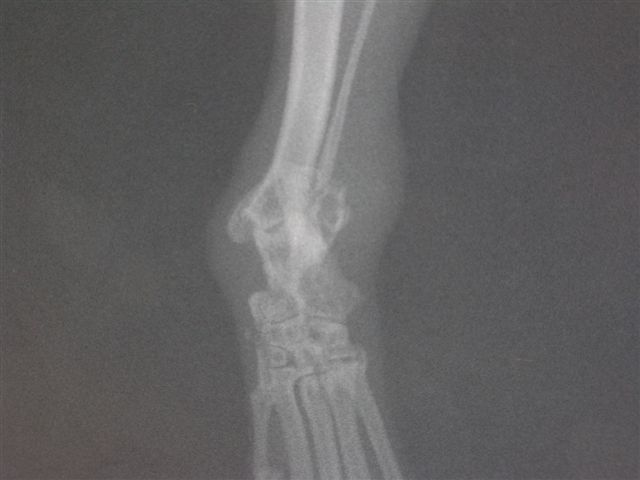

レントゲン写真

右腓骨遠位端の骨折 細い方の骨の先端0.5mmぐらいのところで骨折している

内側に変位しているが、問題なし。周りの皮膚が腫れているのがわかる。

処置 抗生剤と消炎剤で様子見る。完全に変位していなければ、ギブス、手術をしない方が予後がよい。

2週間から1ヶ月で完治する

環境中に骨折の原因があるので対策する。高いところから落ちていないか、手足を引っ掛けていないかなど。